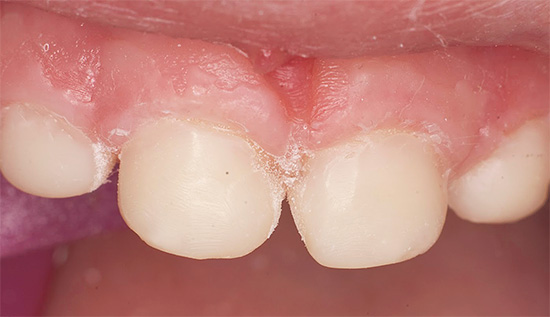

Foto dei denti con carie in bottiglia prima e dopo il trattamento:

Nella fase di una macchia bianca o debolmente pigmentata, è spesso possibile ripristinare quasi completamente l'area dello smalto danneggiata utilizzando metodi di terapia rimineralizzante. A casa, i denti vengono regolarmente trattati con gel speciali come R.O.C.S. Medical Minerals o GC Tooth Mousse. Ma non si può decidere il trattamento da soli con il loro aiuto: solo il medico dovrebbe determinare lo stadio di sviluppo della carie e prescrivere un trattamento.

I metodi professionali sono più efficaci nelle prime fasi dello sviluppo della carie in bottiglia, quando il medico tratta la superficie porosa dello smalto danneggiato con speciali infiltranti (sistema ICON). Tale procedura richiede 1-1,5 ore di tempo, è piuttosto laboriosa, richiede l'uso di una tenda di gomma (diga di gomma) e nei bambini piccoli viene eseguita in anestesia generale.